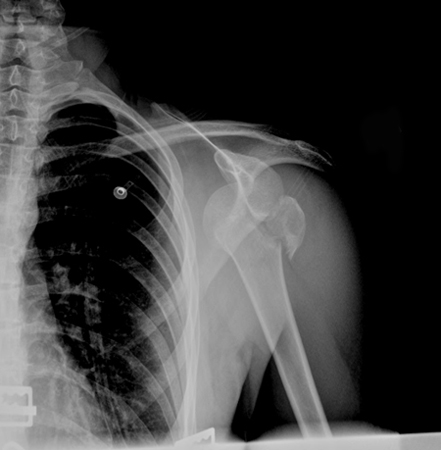

Scapular Y x-ray view showing an anterior fracture dislocation of the shoulder and fracture of the greater tuberosity

Personal collection of Dr Paul Novakovich